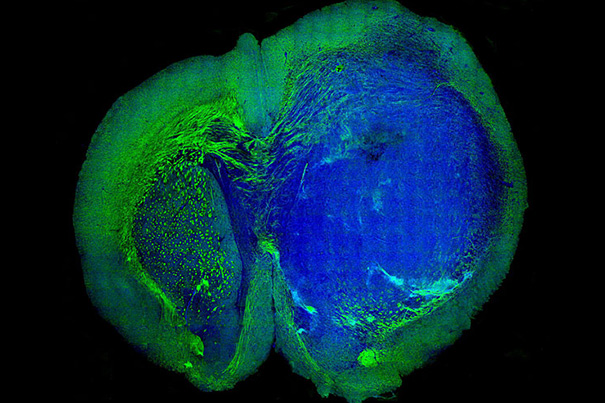

Insight into seeing

Harvard-affiliated researchers have been able to make a comparison of neurons in optic nerves to learn more about why some regenerate and others don’t.